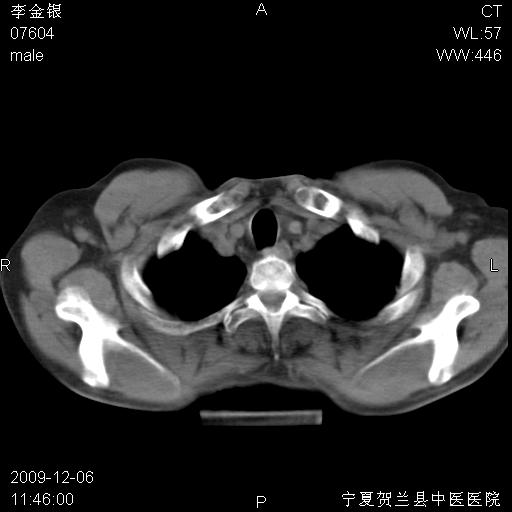

该病人 ,男,62岁,主因咳痰带血两天

支气管壁明显增厚 管腔狭窄,腔静脉后多个淋巴肿大,结合年龄病史考虑右肺上叶中央型肺癌并阻塞性肺炎

右肺上叶后段支气管阻塞,右上肺门占位,相应肺段阻塞性肺炎,右肺门有淋巴结肿大。诊断右肺上叶中心型肺癌,阻塞性肺肺炎、右肺门淋巴结转移。

考虑右侧中央型肺癌伴右肺上叶后段阻塞性炎症、肺不张、右肺门和纵隔淋巴结肿大。

右肺上叶中心型肺癌,阻塞性肺炎、右肺门和纵隔淋巴结转移。